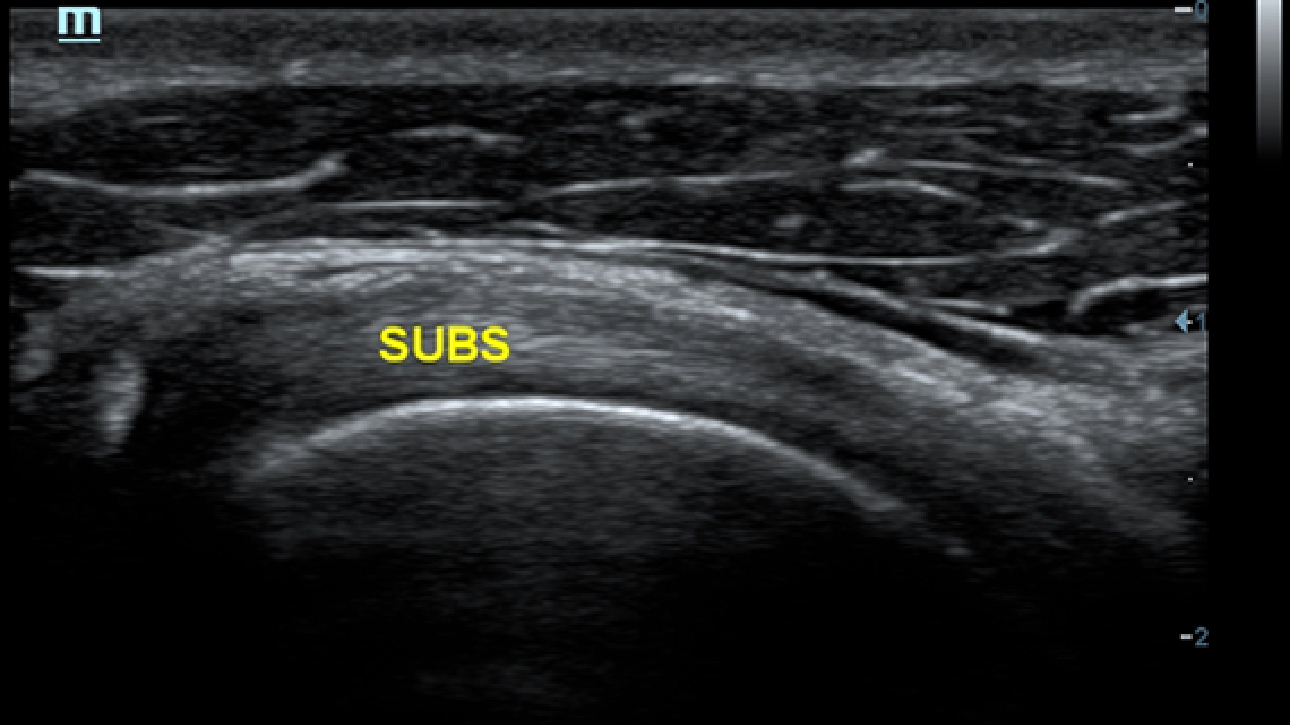

X-Insight, daha geli?mi? g?rĂŒntĂŒler elde etmek i?in kapsaml? bir ??zĂŒmdĂŒr.

Mindrayâin yeni ??zĂŒmĂŒ, geli?en en yeni ultrason teknolojileri ile birlikte, mĂŒ?terilerin g?rĂŒ?lerini klinik gerekliliklerle tam anlam?yla birle?tiren bir ??zĂŒmdĂŒr. Taptaze bir ruhla, gelece?e odaklanarak ve s?n?rs?zl???n pe?inde ko?arak, artan ?l?eklenebilirlikte sĂŒrekli olarak geli?en bir ??zĂŒmdĂŒr.

?ok y?nlĂŒ bir partner olarak, X-Insight'l? DC-60 Exp, her y?nĂŒyle gĂŒnlĂŒk klinik uygulamay? kolayl?kla ve belirsizlik olmadan y?netmenize yard?mc? olacak kapsaml? bir ??zĂŒm sunar.

MĂŒ?teri gereksinimlerine y?nelik g?rĂŒ?ler temelinde, X-Insight'l? DC-60 Exp, eXpress Clarity, eXceptional Intelligence ve eXceeding Experience ile gĂŒ?lendirilerek, hassas g?rĂŒntĂŒlemeyle yĂŒksek verimlilik sa?layacak ?ekilde tasarlanm??t?r.